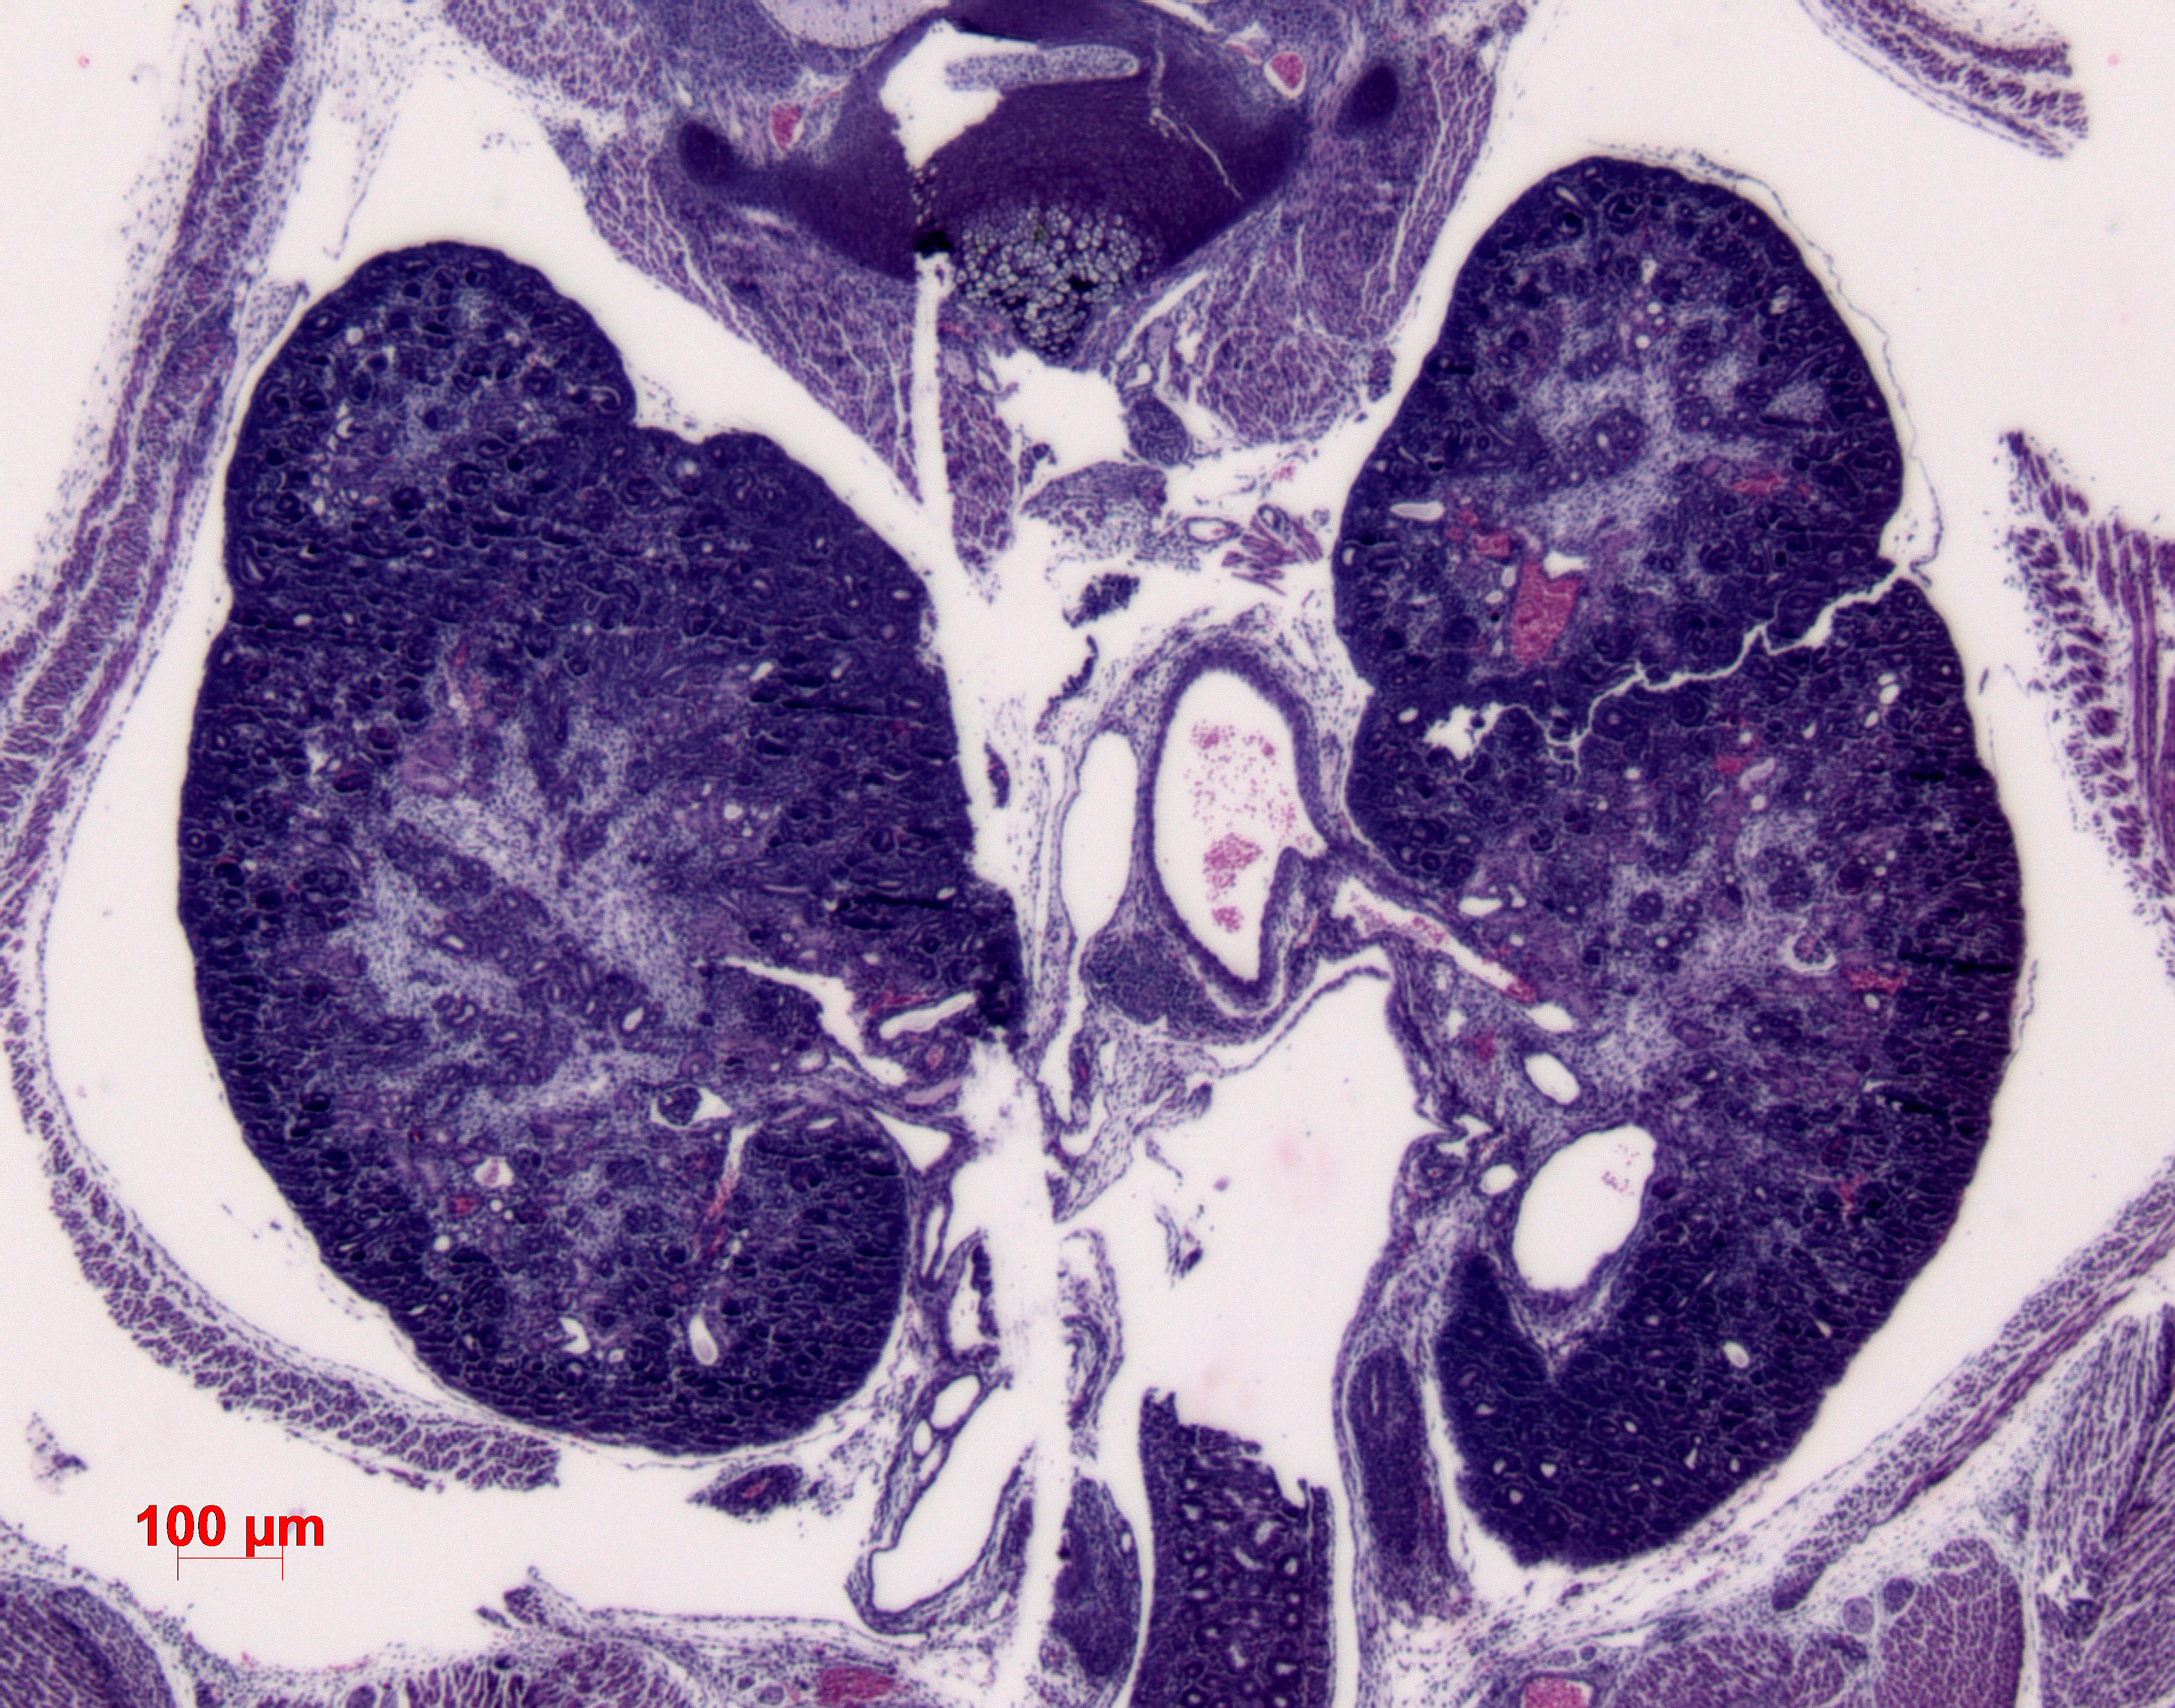

Caption Mutant 1200-007-2 shows bilateral duplex kidneys and hydroureter